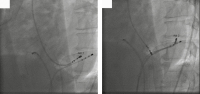

Abbildung 3: Ablationssitus: 60° LAO-Projektion: Links: Endokardiale Ablation über retrograden aortalen Zugang (Abl 1). Rechts: Epikardiale Ablation über Coronarsinus (Abl 2).